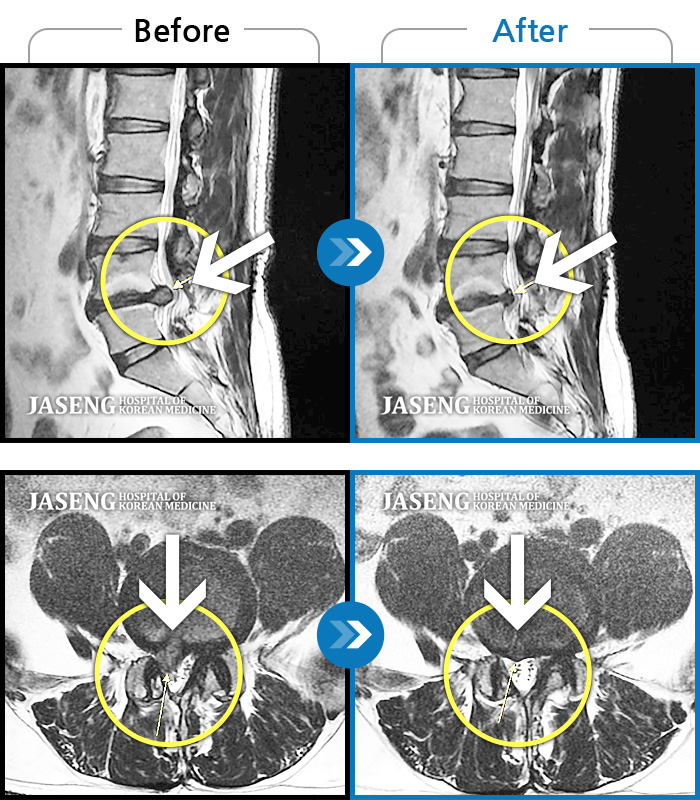

허리디스크

울산 · 정운석 원장

양측 하요추부 통증과 우측 하지 저림

촬영시기

2022.03.16 ~ 2022.11.12

2023.01.19